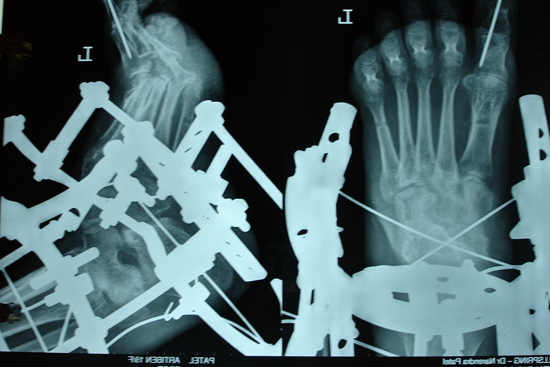

TEV

Aarti

Gulam Rasul